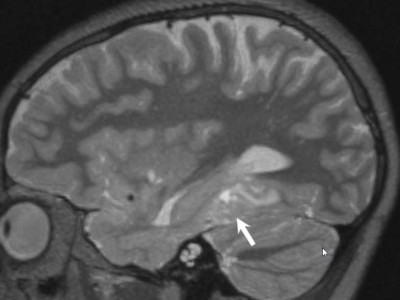

Hirntumor bei einem Kind

Ein Krampfanfall mit Bewusstseinsverlust führten einen 11-jährigen Jungen in die Klinik. Im MRT zeigte sich ein Hirntumor – doch um welche Erkrankung handelte es sich genau? Eine Kasuistik (auf englisch).

Magnetresonanztomographie/© Svitlana / Stock.adobe.com (Symbolbild mit Fotomodell), Schaumiges Bronchialsekret bei akutem Lungenödem/© Eichner M. doi.org/10.1007/s00063-025-01258-9 unter CC-BY 4.0, Intrazerebrale Blutung nach mechanischer Thrombektomie/© Mohamad J / all rights reserved Springer Medizin Verlag GmbH, Intrakranielle Abszesse/© Seidl H et al. doi.org/10.1007/s00108-025-01863-y unter CC-BY 4.0, Bildtitel/© Klaus Eppele / stock.adobe.com (Symbolbild mit Fotomodell), Seniorin liegt reglos auf Boden/© Racle Fotodesign / stock.adobe.com (Symbolbild mit Fotomodell), Tumor im linken Kleinhirnbrückenwinkel und inneren Gehörgang (linkes Bild) und Tumor am Foramen jugulare (rechtes Bild)/© Springer Medizin, Eine Frau im MRT/© Maksym Povozniuk / stock.adobe.com (Symbolbild mit Fotomodellen), Passantin hilf Frau, die bewusstlos am Boden liegt/© M.Dörr & M.Frommherz / stock.adobe.com (Symbolbild mit Fotomodellen), CT-Aufnahme bei intrakranieller Hämorrhagie/© stockdevil / Fotolia, CT und MRT bei Schädel-Hirn-Trauma/© Springer Medizin Verlag GmbH, Junger Mann liegt auf CT-Liege/© LStockStudio / stock.adobe.com (Symbolbild mit Fotomodell), Lesion in the right-sided medial occipitotemporal gyrus/© Springer-Verlag GmbH, Frau bei Strahlentherapie/© (M) Mark Kostich / Stock.adobe.com (Symbolbild mit Fotomodellen), Search Icon, CT-Pulmonalisangiographie/© Das M et al. doi.org/10.1007/s00117-016-0100-3 unter CC-BY 4.0, Kanüle für Katheterbehandlung/© romaset / stock.adobe.com, Alter Mann in Sprechstunde mit junger Ärztin/© lordn / Stock.adobe.com (Symbolbild mit Fotomodellen)